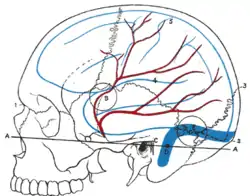

Relations of the brain and middle meningeal artery to the surface of the skull. | |

The anterior branch of the middle meningeal artery runs beneath the pterion. It is vulnerable to injury at this point, where the skull is thin. Rupture of the artery may give rise to an epidural hematoma. In the dry cranium, the middle meningeal, which runs within the dura mater surrounding the brain, makes a deep groove in the calvarium.

An injured middle meningeal artery is the most common cause of an epidural hematoma. A head injury (e.g., from a road traffic accident or sports injury) is required to rupture the artery. Emergency treatment requires decompression of the haematoma, usually by craniotomy. Subdural bleeding is usually venous in nature, rather than arterial.

The middle meningeal artery runs in a groove on the inside of the cranium. This can clearly be seen on a lateral skull X-ray, where it may be mistaken for a fracture of the skull. On a dry specimen, the groove is easy to see. This means that the artery is easy to study, even in specimens centuries old, and several classifications of the branches have been proposed, e.g. Adachi's classification of 1928.